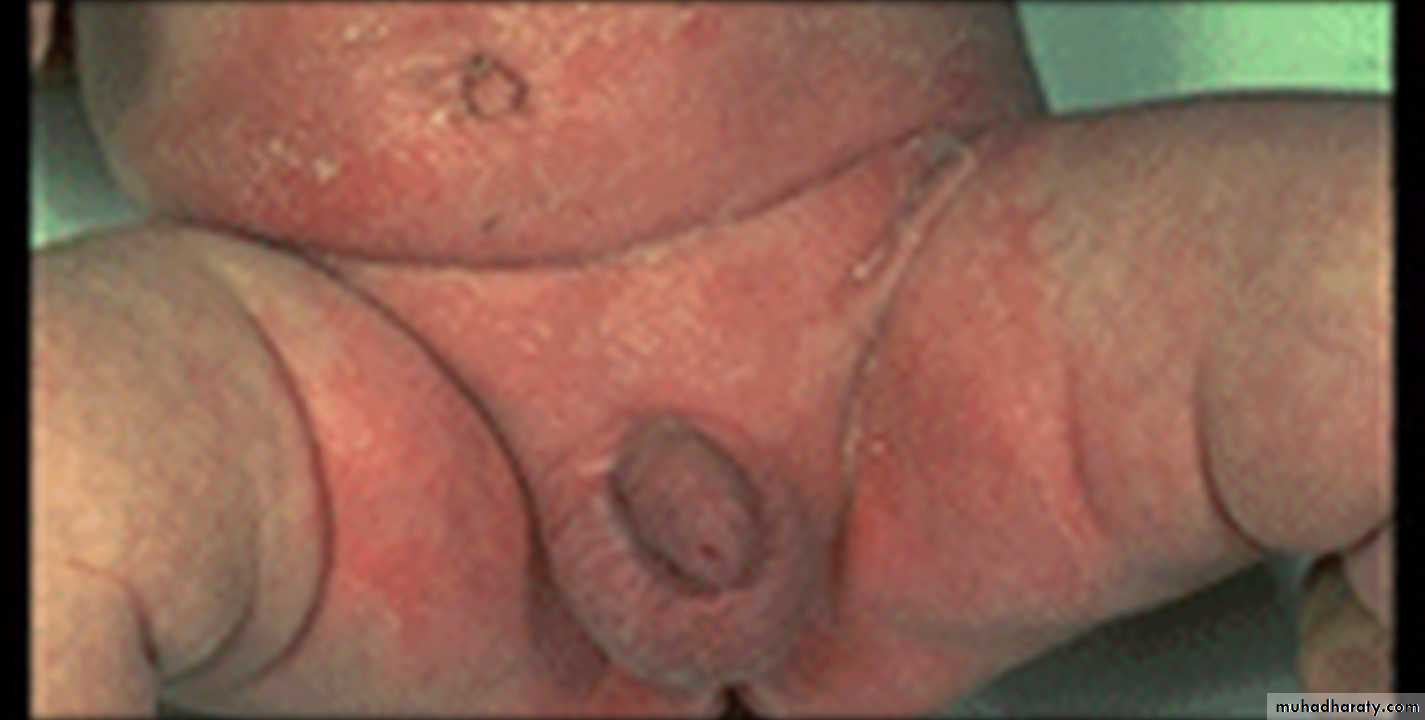

Napkin (diaper) dermatitis

This is a primary irritant effect of body fluids on the skin. The eruption is essentially confined to the area in contact with the diaper.

It is very common in infancy

(but could affect old people who use diapers).

caused by contact with urine & faeces ( bacteria in the last split urea (in urine) to ammonia which is very irritant.

the area (especially convex areas) is mildly to intensely errythematous, macerated ± papules, vesicles& ulcers.